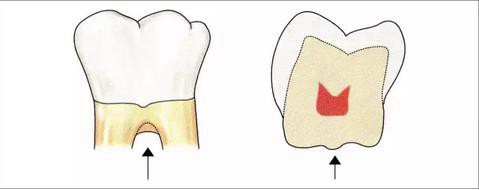

釉突:

釉突是指牙釉質(zhì)延伸到分叉部上方的狀態(tài),這個現(xiàn)象在下頜后磨牙中出現(xiàn)的頻率較高。如果存在釉突的話,那這個部分就不會生長結(jié)締組織。為此就會由于牙垢的累積而造成牙周炎的形成,很容易發(fā)生牙周附著喪失。

根據(jù)Grewe等的文獻,可以對釉突的存在進行以下的分類。

·釉突的分類

I度:釉突向根分叉部略微延伸的狀態(tài)。

II度:釉突向根分叉部延伸,沒有到達的狀態(tài)。

III度:釉突延伸到根分叉部的狀態(tài)。

·釉突的發(fā)生頻率

下頜磨牙:約30%

上頜磨牙:約17%

▼圖4 釉突的分類

也就是說在口腔外科,無論是切除療法還是再生療法,都會采取將釉突切除,將根面的牙骨質(zhì)露出,期待在術(shù)后的牙周組織可以擁有健全的附著狀態(tài)的方法。